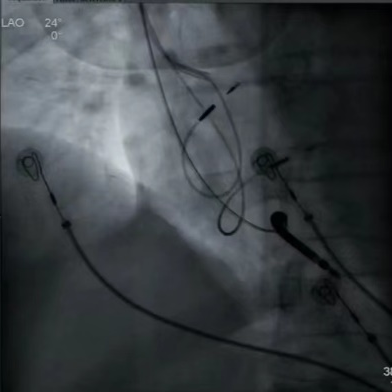

活动于全国五家知名中心开展直播:温州医科大学附属第一医院黄伟剑教授、苏蓝教授;厦门大学附属心血管病医院常栋教授、蔡彬妮教授、李桂阳教授、黄淑芬教授、;浙江大学医学院附属邵逸夫医院盛夏教授、叶炀教授、王敏教授;上海交通大学医学院附属同仁医院邱朝晖教授、吴献豪教授与复旦大学附属中山医院陈学颖教授;中山大学孙逸仙纪念医院医院陈样新教授、周淑娴教授、麦憬霆教授(按手术直播排序)。

五家直播中心联手参与,为大家带来了手术直播和MINI TALK等丰富多彩的内容。每个中心都带来了自己的经验和技术,与主持专家进行交流和讨论,分享了手术策略、操作步骤以及手术细节和技巧。

术中HIS电极影像

LBB影像位置

术中影像 HIS-HISD-消融靶点